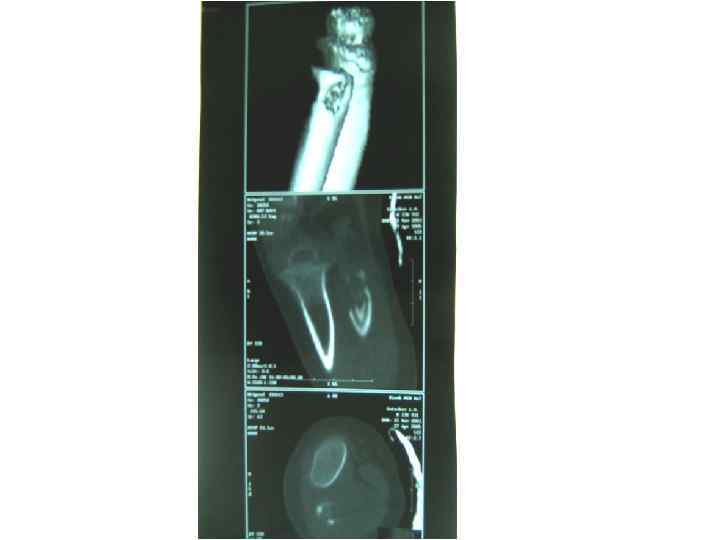

Туберкулезный коксит • Туберкулёз правого тазобедренного сустава. Секвестры тела подвздошной и головки бедренной костей, скопление экссудата в полости сустава и образование параартикулярного абсцесса. • рентгенограмма; • компьютерная томограмма; • магнитно-резонансная томограмма.

Туберкулезный гонит Туберкулёзные оститы эпифизов больше- и малоберцовой костей • прямая рентгенограмма; • компьютерная томограмма